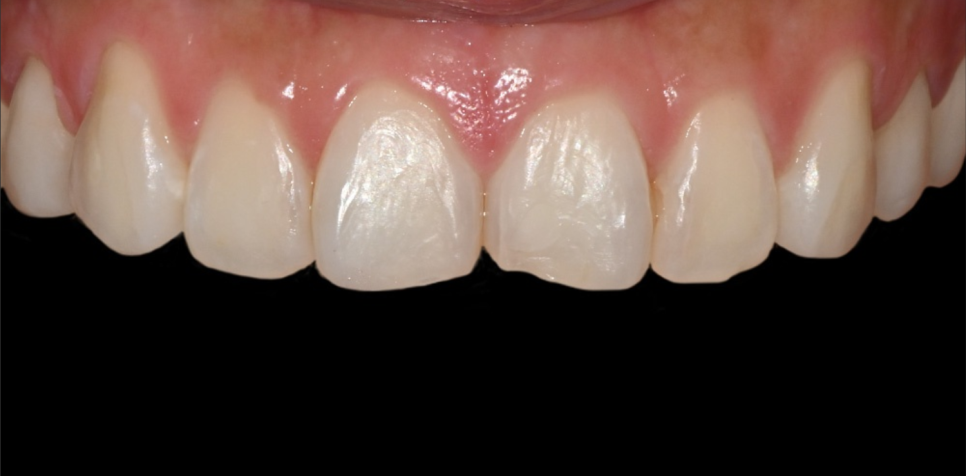

Condition at the time of the visit

The patient did not have any existing prosthetics, but the line between the front teeth was uneven and the brightness was not consistent, so they said they had always been concerned about their front teeth in photos.

Since the front teeth are the first thing seen in the overall appearance, even a slight difference in tone can completely change the impression.

For this patient, a more natural smile could be created by harmonizing the color, line, and length.